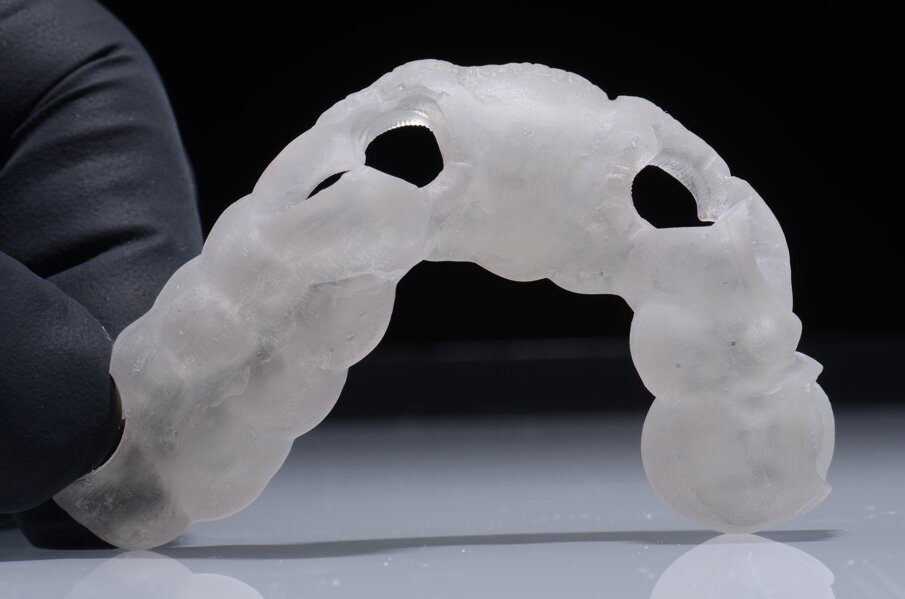

Dobbiamo quindi essere in grado, una volta definita la posizione corretta dell’impianto, di trasferire tutto clinicamente e di realizzare una fase chirurgica che possa rispettare tale programmazione. Voglio dunque ricavare dal progetto una dima chirurgica da utilizzare durante l’intervento: preparare il letto implantare e inserire l’impianto attraverso le guide consente di essere precisi e di realizzare l’intervento senza rischi. La dima chirurgica è realizzata attraverso stampanti 3D che oggi sono diventate molto affidabili. Le dime prodotte vengono controllate e posizionate su modelli stereolitografici ricavati dall’estrapolazione dei file STL direttamente da CoDiagnostiX, il software di chirurgia computer assistita di Dental Wings. La dima chirurgica adattata sul modello ci consente di verificarne, attraverso le finestre di ispezione, la congruità. Se la dima è precisa sul modello allora possiamo pensare di poter utilizzare lo stesso principio subito dopo il posizionamento implantare.

Il nostro obiettivo è quello di riuscire a dare alla paziente un provvisorio immediato nell’arco di due ore. Questo diventa possibile perché abbiamo utilizzato un flusso digitale fin dall’inizio. In laboratorio vengono realizzate la dima chirurgica (Figg. 16, 17), la dima protesica (Fig. 18) e anche il provvisorio (Figg. 19-21) che contiene delle alette di riposizionamento. Il tutto gestito con modelli digitali sui quali saremo in grado di funzionalizzare il provvisorio post-chirurgico (tecnica DIL). In un caso come questo se utilizziamo un flusso digitale possiamo evitare subito dopo la chirurgia di rilevare un’impronta degli impianti inseriti. Infatti, utilizziamo una dima chirurgica che ci faciliterà le fasi di intervento. La dima ci consentirà di non fare lembi e nessuna incisione di rilascio (Fig. 22), dopo aver inserito gli impianti (BLX Straumann) (Figg. 23-31) e aver controllato il loro alloggiamento, inseriamo sugli stessi dei transfert da impronta (Fig. 32).

Fig. 16 - Disegno dima chirurgica.

Fig. 17 - Dima chirurgica.

Alloggiamo la dima protesica (Fig. 33), e blocchiamo i transfert con della resina trasparente (tecnica DIL) (Figg. 34, 35). In questo modo possiamo far riposare il paziente in studio dopo appena 35 minuti dall’inizio dell’intervento. La dima protesica, infatti (Fig. 36) con i transfert inseriti viene completata con l’unione degli analoghi ai transfert (Fig. 37). L’insieme così composto viene riadattato sul modello master digitale iniziale (Figg. 38-40) sul quale era stata costruita sia la dima chirurgica che la dima protesica come anche il provvisorio. Gli analoghi vengono bloccati sul modello con resina trasparente (Figg. 41-43). Alloggiamo il provvisorio sul modello master digitale così ottenuto (Figg. 44, 45).